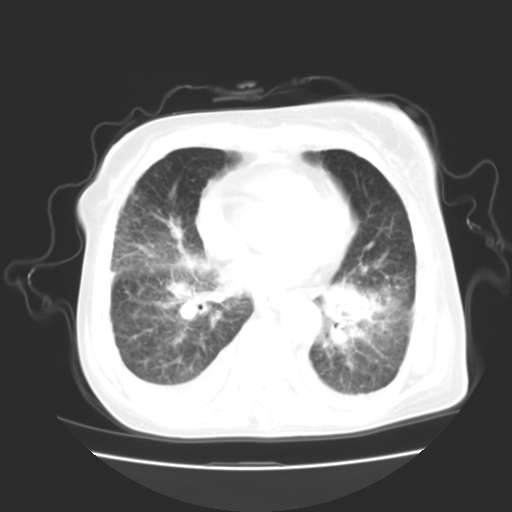

女70y乳腺ca(针吸活检)

多部位转移瘤的诊断可以肯定,我的疑问是:双肺对称高密度影及胸水是否为心衰肺水肿,病人体虚弱,不好意思图象传的乱![em9]

1)左侧乳腺癌并左侧腋窝及纵隔淋巴结转移,两肺淋巴道转移(癌性淋巴管炎),肝脏多发性转移。2)双侧胸腔积液。3)慢性胆囊炎。

1、左侧乳腺癌;

2、左腋窝、纵隔淋巴结肿大(转移性);

3、双肺癌性淋巴管炎;

4、双侧胸腔积液(考虑淋巴回流障碍所致);